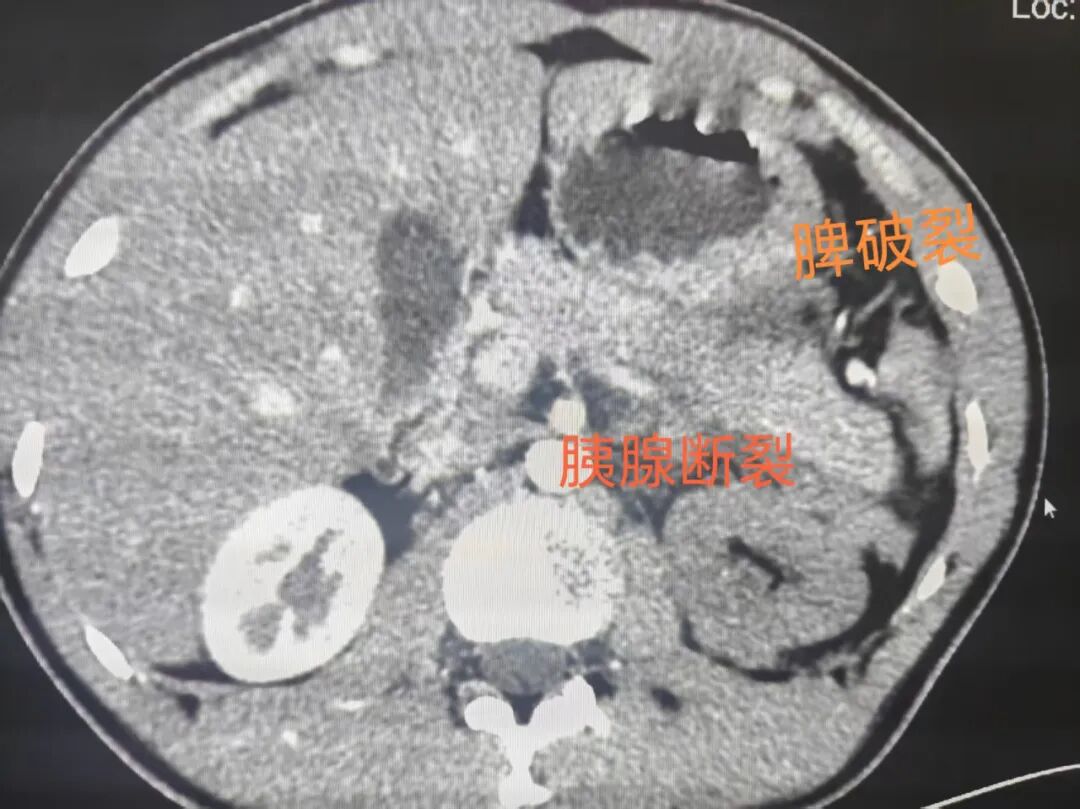

为了排查可能危及生命的隐匿损伤,杨坤当机立断:“立即安排强化CT检查,我亲自陪着去!”在他的全程陪同下,检查快速推进。结果出来的那一刻,所有人都倒吸一口凉气——江措胰腺尾部断裂、脾破裂、左侧肾上腺破裂,多脏器同时受损,已处于危急状态,必须马上进行手术治疗!

然而,新的难题接踵而至。此类多脏器损伤手术,操作难度极高,对医疗设备和技术水平都有严苛要求,而贡觉县人民医院的医疗条件相对有限;若想转入上级医院,至少需要一天一夜的路程,江措的身体根本无法承受长时间转运的颠簸和风险,随时可能因失血性休克、脏器衰竭而失去生命。

手术台上,杨坤凭借精湛的外科技术和稳定的心态,精准操作,仔细处理断裂的胰腺尾部,修补破裂的脾脏和肾上腺……手术室内,只有器械碰撞的清脆声响和医护人员沉稳的呼吸声,所有人都为了同一个目标——挽救江措的生命。